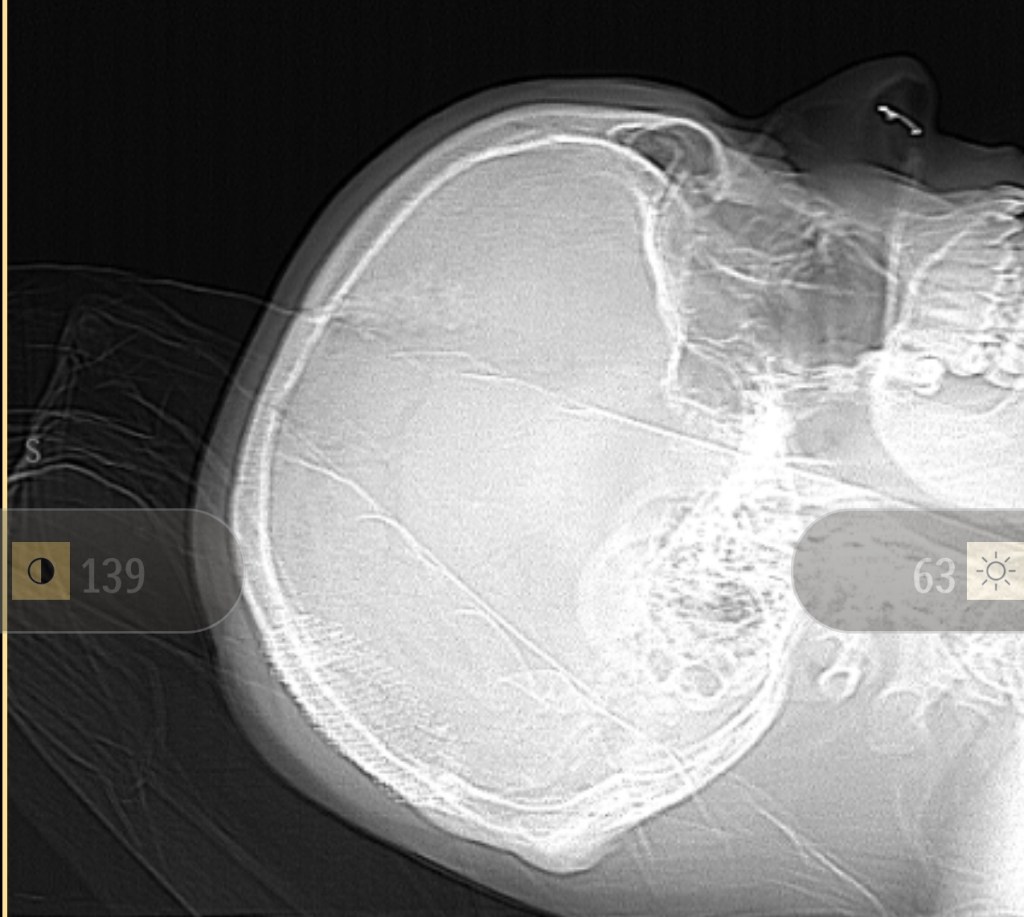

To remind everyone about the size and location of the tumor

The tumor from the above view

The MRI looked good. Since they couldn’t take out the whole tumor without cutting into that main blood vessel they showed how small his Neurosurgeon was able to get it which looks like it was 2.1cm X 0.9 cm. Beyond that, everything looks on track for a person who had surgery 24 hours ago.